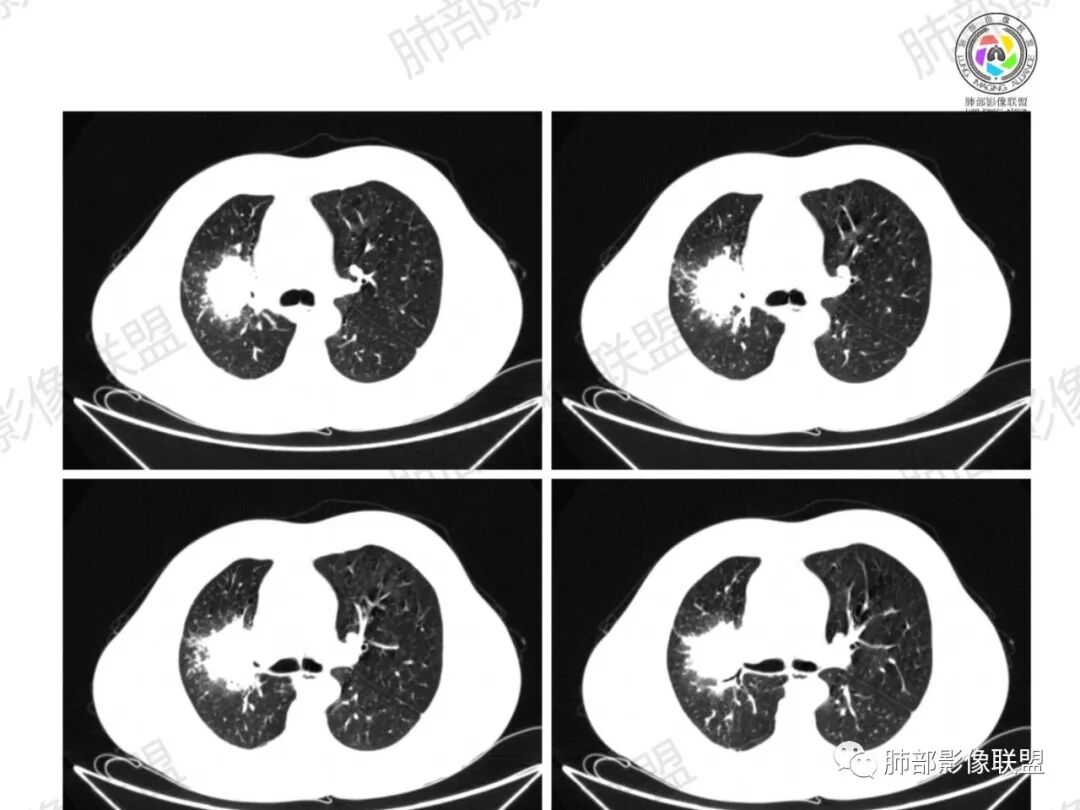

了:中年男性,右肺门肿块影,浅分叶,周围晕征,边缘清楚,小叶间隔增厚,树芽征,支气管截断,不均匀强化,内可见低密度坏死,纵隔淋巴结肿大,综合考虑肺部肿瘤并阻塞性肺炎

一切∮随缘:右肺门肿块影形态不规则,边缘毛糙,右肺上叶支气管堵塞,病变跨叶生长,远端血管束增粗,周围散在多发结节,部分位于胸膜下,平扫密度尚均匀,增强后不均匀强化,呈中度强化,坏死区无强化,纵隔淋巴结肿大。临床无感染症状,考虑恶性,鳞癌,腺癌,鉴别慢性脓肿。

那个人:中年男性,右肺肿块影,支气管截断,截断口非圆盾,病灶膨隆分叶,坏死,强化。病灶内血管破坏。病灶远端树芽及小结节影,考虑恶性,鉴别结核

周太狼:中年男性,吸烟史,陈旧结核史,呼吸道症状未提及,抗感染治疗无效。影像见右上肺门区软组织肿块影,浅分叶、毛刺,支气管似有截断,其内密度不均匀,不均匀强化,内可见低密度坏死区,病壮周围见斑片、结节影。纵隔内淋巴结稍肿大,首先考虑恶性,肺部肿瘤并阻塞性肺炎,肺鳞癌可能,鉴别结核。

弹指之间:中年男性,结核史、吸烟;右肺门肿块,特点:右肺上叶尖、前段支气管狭窄、部分阻塞(肿块大、支气管狭窄闭塞相对轻),肿块内血管部分残留(生长速度快,浸润>破坏),周围见渗出、炎症,部分实变;内见坏死、位于边缘区域;纵隔淋巴结肿大;考虑恶性,1.非支气管粘膜起源首先考虑,淋巴瘤?(但坏死相对多了);2.鳞癌(支气管阻塞轻);3.小细胞待排。

Coke with ice:病变整体收缩平直,毛刺较软,支气管壁增厚。支气管鼠尾状狭窄,于病灶以远可见显示。支气管粘液栓。相邻支气管血管推移明显,磨玻璃边缘模糊,多灶坏死边缘清晰,一部分血管自然穿行,猜个炎性病变。

这个比较大的坏死灶,边缘清晰,看似符合鳞癌坏死。仔细看看这个坏死边界,是血管阻挡引起的边界清晰。其他的病灶内低密度是柱形粘液栓。实性部分强化有轻度延迟强化。病变背景是双上肺的小叶中心结节。病变区的支气管壁是厚的。

妞妞:右肺门区病灶,边缘有GGO,模糊,远端树芽,支气管受阻,有圆钝感,病灶坏死,边缘清楚,实性成分有强化,不像鳞癌强化,首先考虑结核,鳞癌待排,建议支气管镜

良孑:右肺门肿块,有平直,u型凹陷及尖角征,远端可见散发树芽征,有支气管截断,肿块内坏死边界清,似可见围绕坏死的环状强化,综合分析首选炎性病变,TB可能,冇吸烟史,良恶性征象都有鳞癌要鉴别,